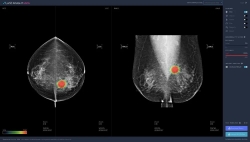

| Hàn Quốc thành công với đột phá công nghệ AI trong cuộc chiến chống ung thư Thông tin từ báo Donga Ilbo ngày 17/8 cho biết, một bước tiến đột phá trong lĩnh vực y tế đã được ghi nhận tại ... |